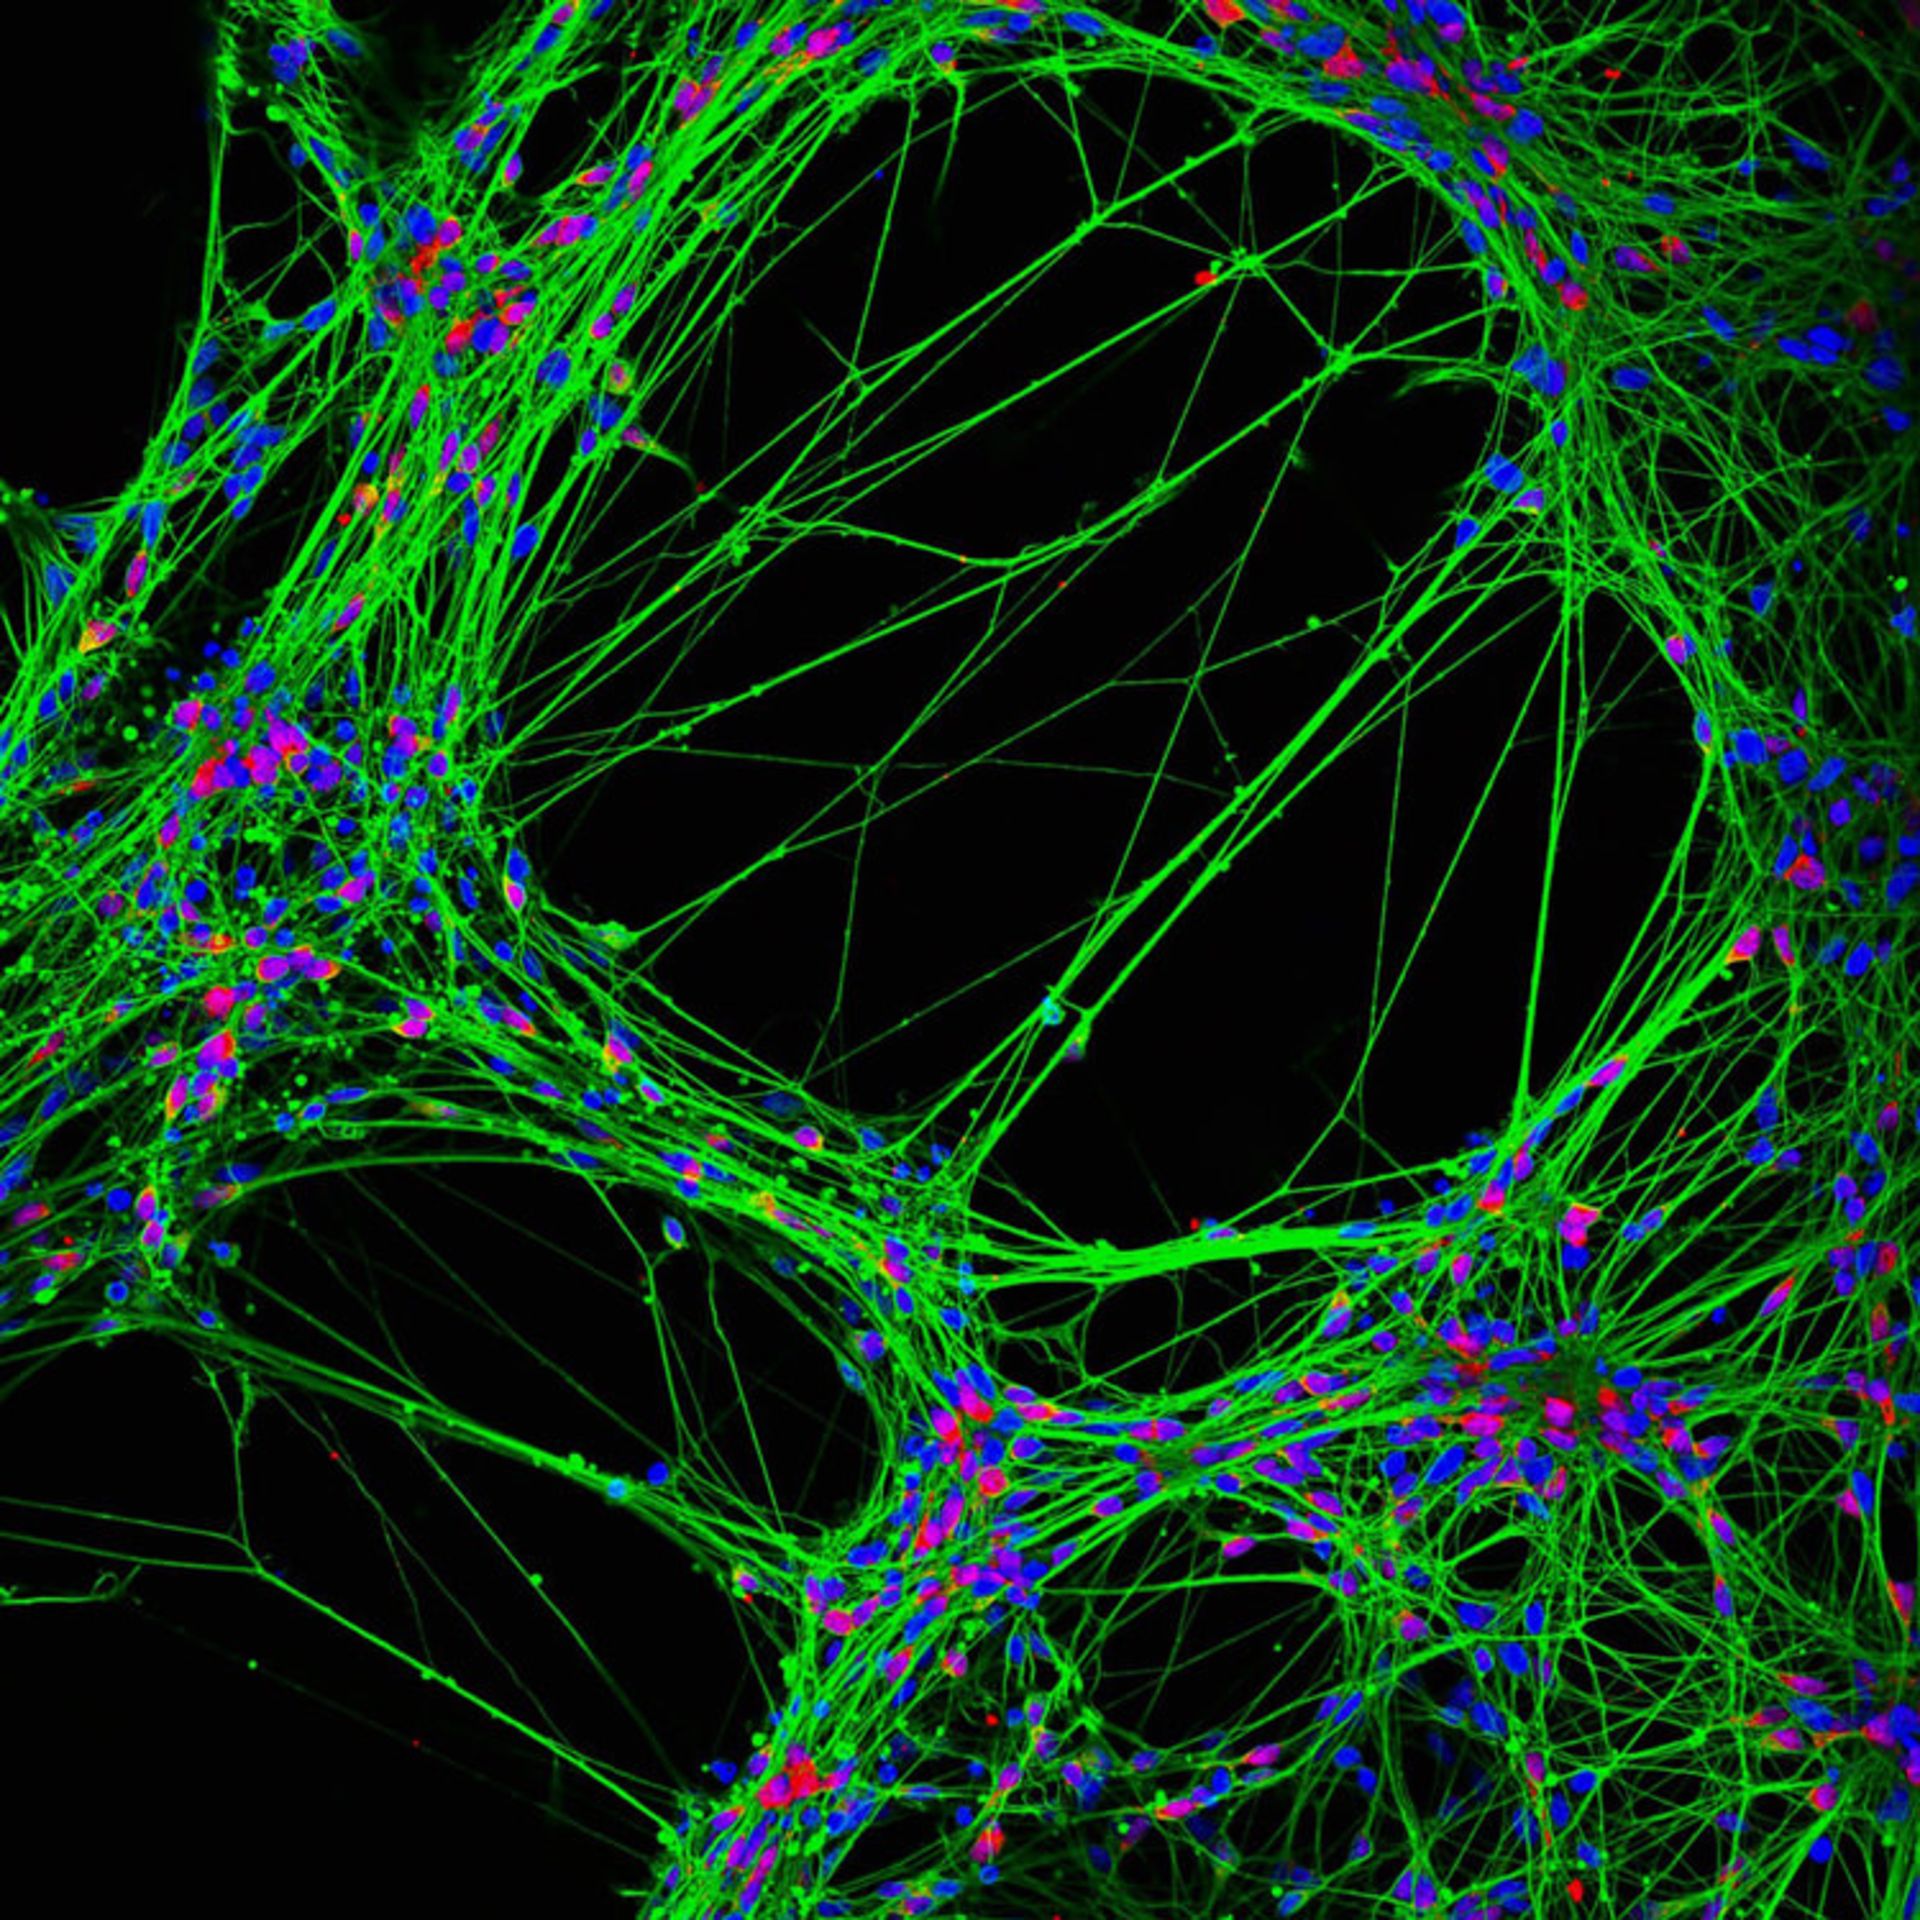

نورونهای انسانی حاصل از سلولهای بنیادی عصبی؛ بزرگنمایی ۲۰ برابری

جیانگان جائو (Jianqun Gao) از استرالیا